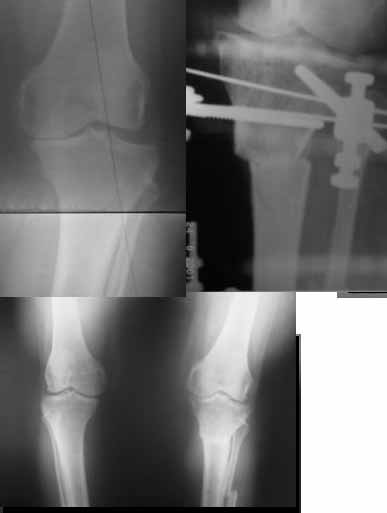

I do upper tibial osteotomies with either an ilizarov fixator and acute correction of the deformity or with an orthofix with gradual correction.

Sending you pics of the steps of the osteotomy and the frame.

You can do the osteotomy in a "focal dome" or in a transverse fashion. The dome has the advantage of having a good contact, allowing weight bearing as tolerated early on.

The level is below the tibial tuberosity.

Since the center of rotation of these deformities is usually near the knee joint line, lateral translation of the distal fragment is necessary to normalise all the axes.